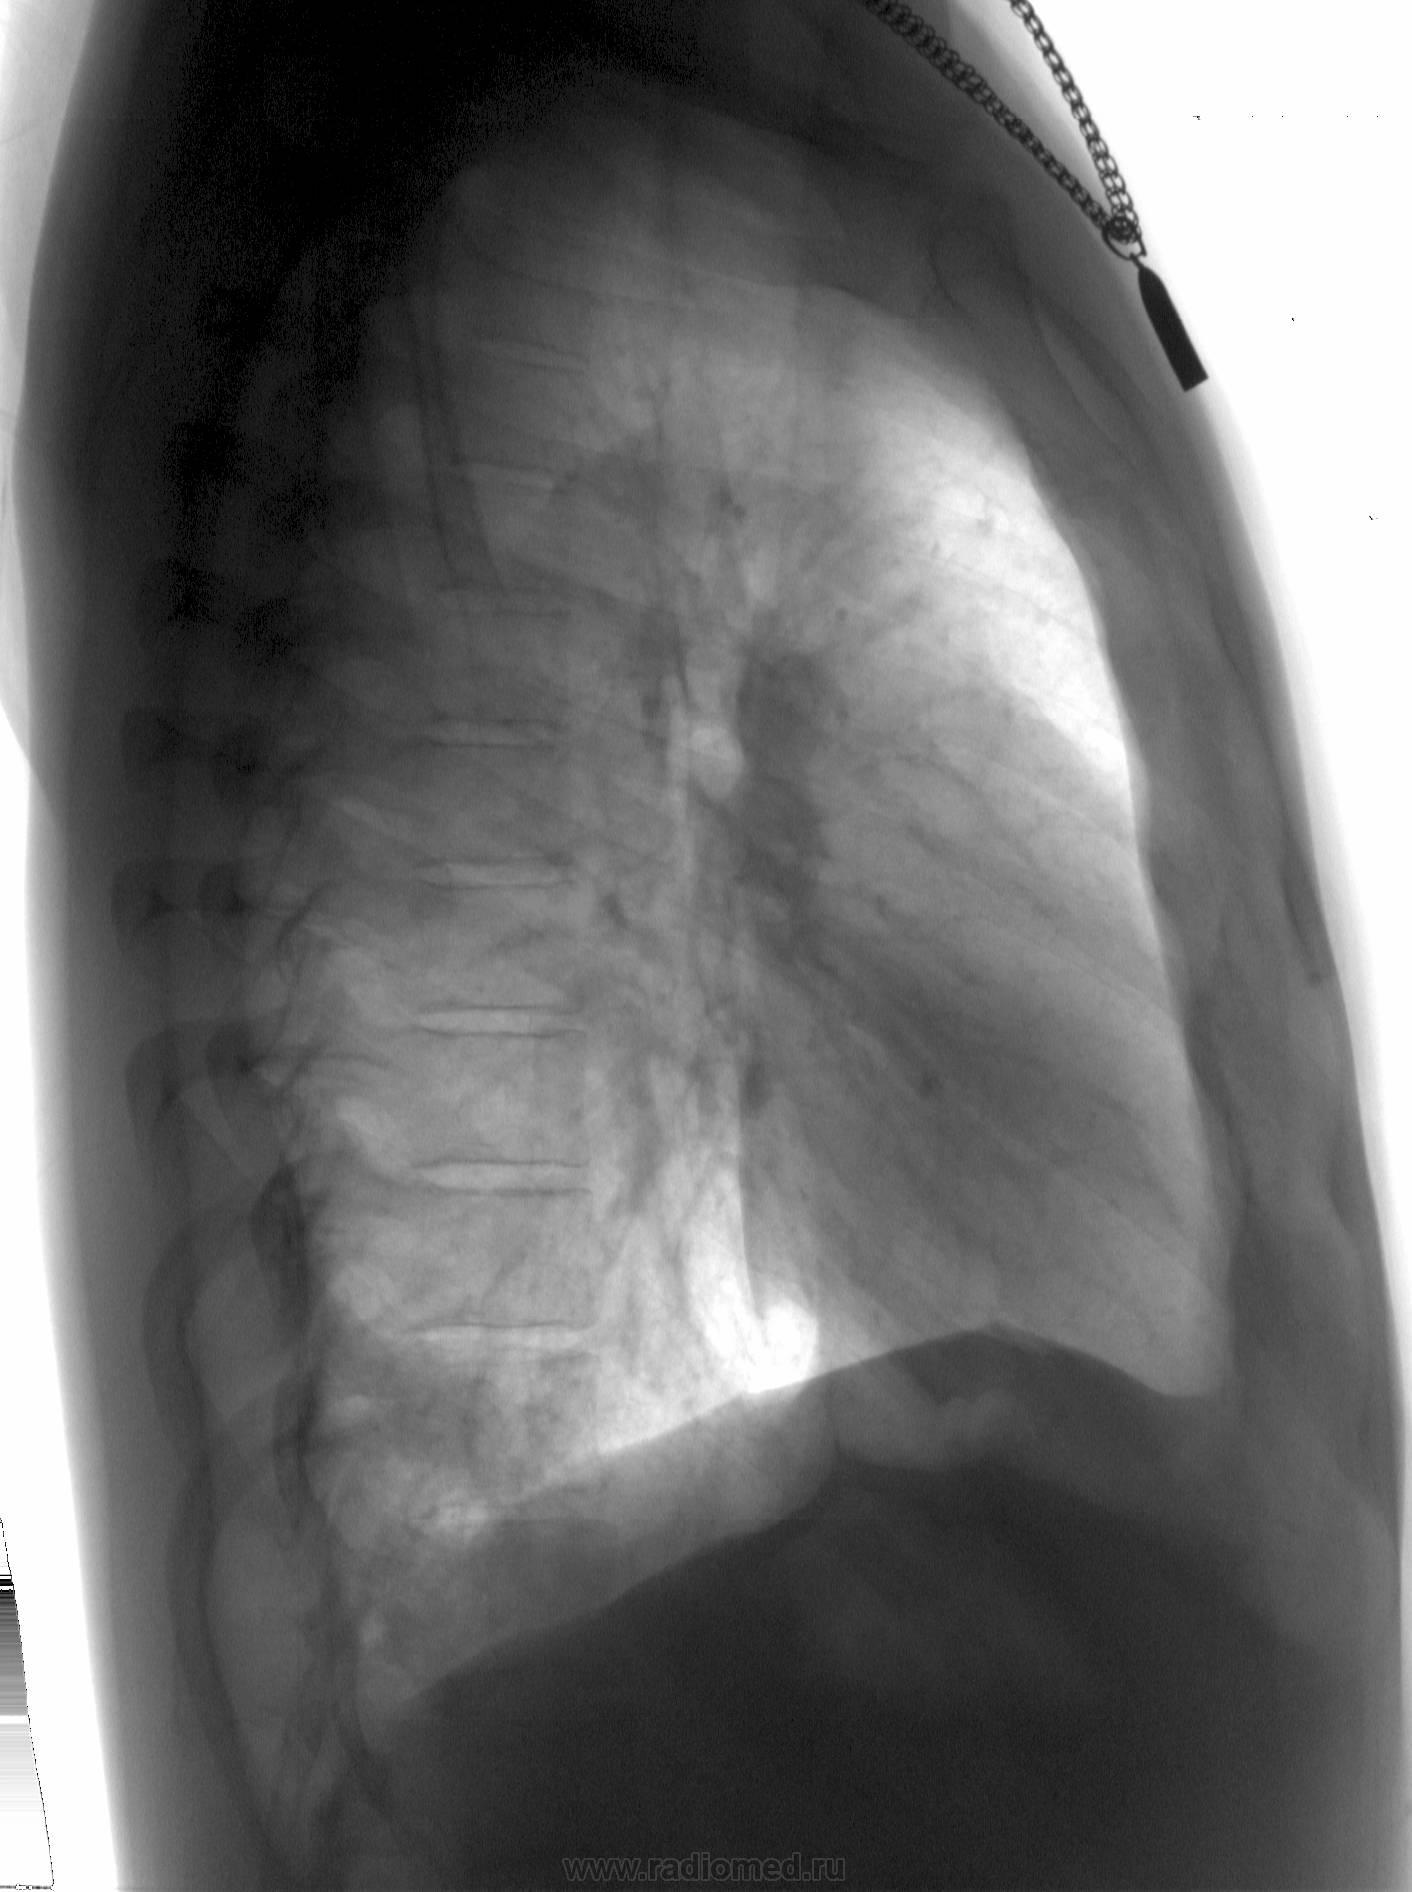

Молодой человек 30 лет. Проводил ц ФГ в 2010 году, после чего был направлен на дообследование (КТ). Сейчас пришел на контроль, протокол КТ предстваил лично.

От бокового снимка отказался...увы. Что скажете?

Шаровидная тень: в S4 в/доли слева (1 случай) и S10 н/доли справа (2 случай)

Татьяна Валентиновна, асолютно согласен. что основной рентгенологический признак - шаровидные тенеобразования, но...достаточно ли они "шаровидны" и достаточно ли однородны....+молодой, в общем то возраст, + отсутствие существенных жалоб. Конечно, смущает тот факт, что это не первые их ФГ (но у меня то они впервыеwink). Опять же - в С10 (скрывается за тенью печени), в С4 слева (не факт, что раньше было перекрыто левым краем сердца) и, как следствие - не были обнаружены.

Внутрилегочная секвестрация или артериовенозная мальформация.

..... артериовенозная мальформация.

Она самая))). Да, оба случая подтверждены на КТ.

Нечего сказать. Вспомнился мой же №5'). из вопросной ветки... С одной стороны патология видна и на обзорных (в обоих случаях). С другой - с учётом отсутствия жалоб, клиники диф. ряд получился бы немалым. Приоритет диагностики в отношении а/в мальформаций, конечно, у КТ/МСКТ, но гарантирую, что во втором случае с парнем поставил бы (если бы не забыл по такой Rg-картине) эту нозологию далеко не в первых числах...

Со вторым парнем я тоже растерялся...и просто тупо назначил контрольную КТ, и вот надо же было так совпасть, что явились они оба в один день, и парень - на контроль с данными КТ , и барышня - на первичное обследование. Сначала я выставил барышне подозрение на мальформацию и отправил ее на КТ, почти сразу же после нее пришел парень, где выяснилось и его состояние. Данные по барышне поступили на следующее утро. Вот такая история. А заодно - и "закон парных случаев". Так что сработал я самостоятельно - только на 50%, хорошо, что хоть ничего не пропустил по прямому (это к вашим постам по поводу рентгенографии в одной проекции и пользы от цифровой ФГ).